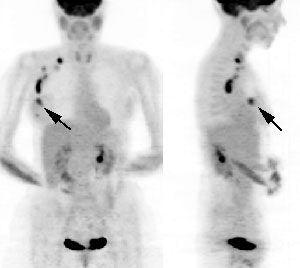

Multifocal breast cancer: The FDG PET exam below is from a patient with a large left breast cancer. The PET exam demonstrated several sites of tracer uptake in the left breast (black arrows). Retrospectively, multiple tumor foci could be identified on the CT scan (white arrows). The presence of multifocal breast cancer can significantly alter patient management. |